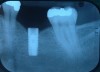

Fig 9. Radiograph depicting fractured screw inside of the implant.

Figure 9